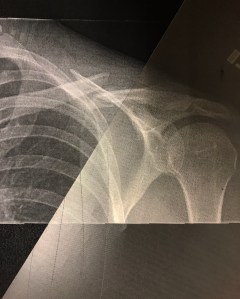

img_0994 February 22, 2017By ryangoold Share this: Share on X (Opens in new window) X Share on Facebook (Opens in new window) Facebook Share on Pinterest (Opens in new window) Pinterest Like Loading...